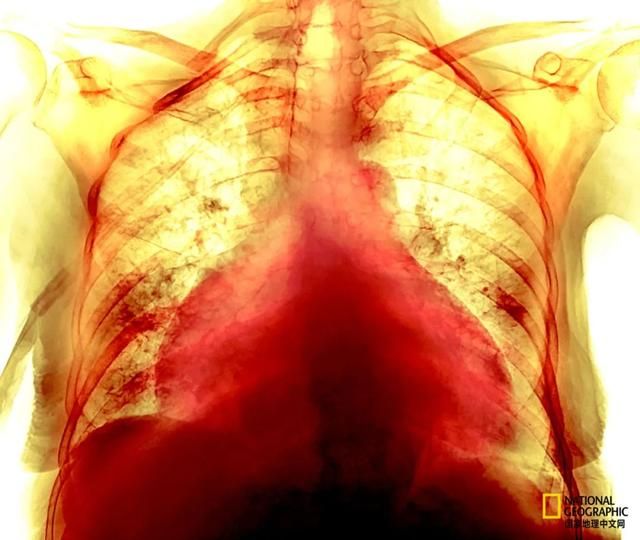

一名74岁女性新冠感染者的彩色X光胸片,一些患者战胜新冠肺炎后数月仍会出现心血管症状,即使他们的胸部扫描和其他检查显示已恢复正常。 摄影:P. MARAZZI/SCIENCE SOURCE 雅典科学院医学研究基金会的免疫学家Evangelos Andreakos,他是冠状病毒病人类基因计划(COVID Human Genetic Effort)国际联合会的成员,该组织一直在寻找特定的基因变异,从而解释为什么一些人从不感染新冠。